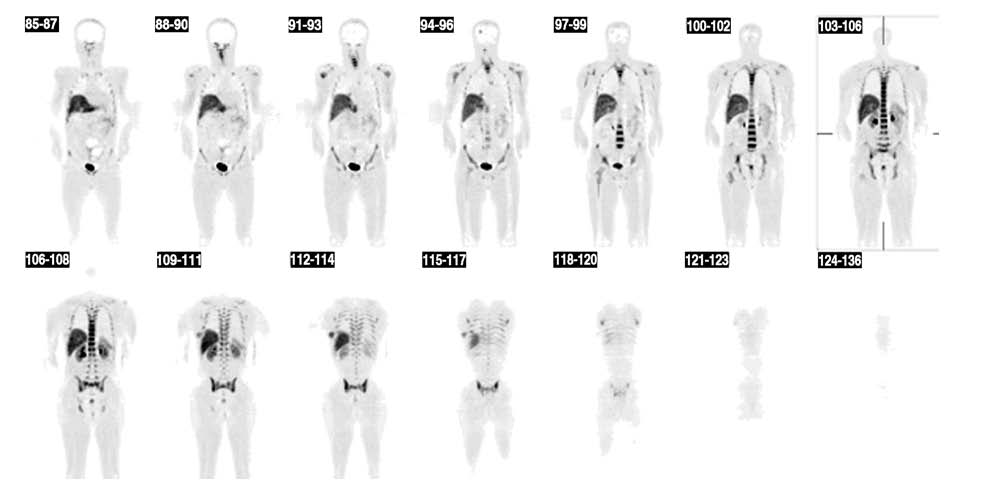

Obr. 1.

Celotělový FLT - PET scan se zřetelným ložiskem zvýšené akumulace radiofarmaka v mozku. Další patologická ložiska v oblasti plic, mediastina a hrudní stěny vpravo laterálně.

Distribuce FLT se za fyziologických podmínek

výrazně liší od distribuce FDG. V obraze dominuje vysoká aktivita

kostní dřeně, jater a sleziny, proto je oblast horní části břišní

dutiny možné hodnotit jenom omezeně (viz obr.1). Aktivita v čase

kontinuálně narůstá (viz obr.2) Na základě provedených scanů

považujeme za optimální čas na akvizice jednotlivých částí 5-30

minut po aplikaci v případě mozku, u celotělového scanu pak 80-120

minut po aplikaci.